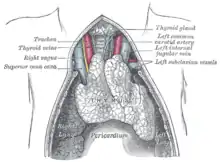

Le thymus est un organe décrit depuis la Grèce antique par Galien, qui y voyait le siège de l'âme. Il est situé entre le cœur et les poumons, et tire son étymologie du grec ancien : θυμός[1],[2],[Note 1], signifiant « excroissance charnue ».

Le thymus est un organe intrathoracique, situé dans la loge thymique, dans le médiastin antérieur[3]. Cette zone est située entre les poumons, et à l'avant du cœur et des gros vaisseaux tels que l'aorte et ses branches[4]. Le thymus est constitué de deux lobes unis par le milieu, sauf à leurs extrémités supérieure et inférieure, appelées les cornes thymiques[5]. Le thymus comprend une région superficielle, appelée « cortex », et une région profonde, appelée « médulla ». Il grandit de la naissance jusqu’à la puberté, puis régresse progressivement[6].